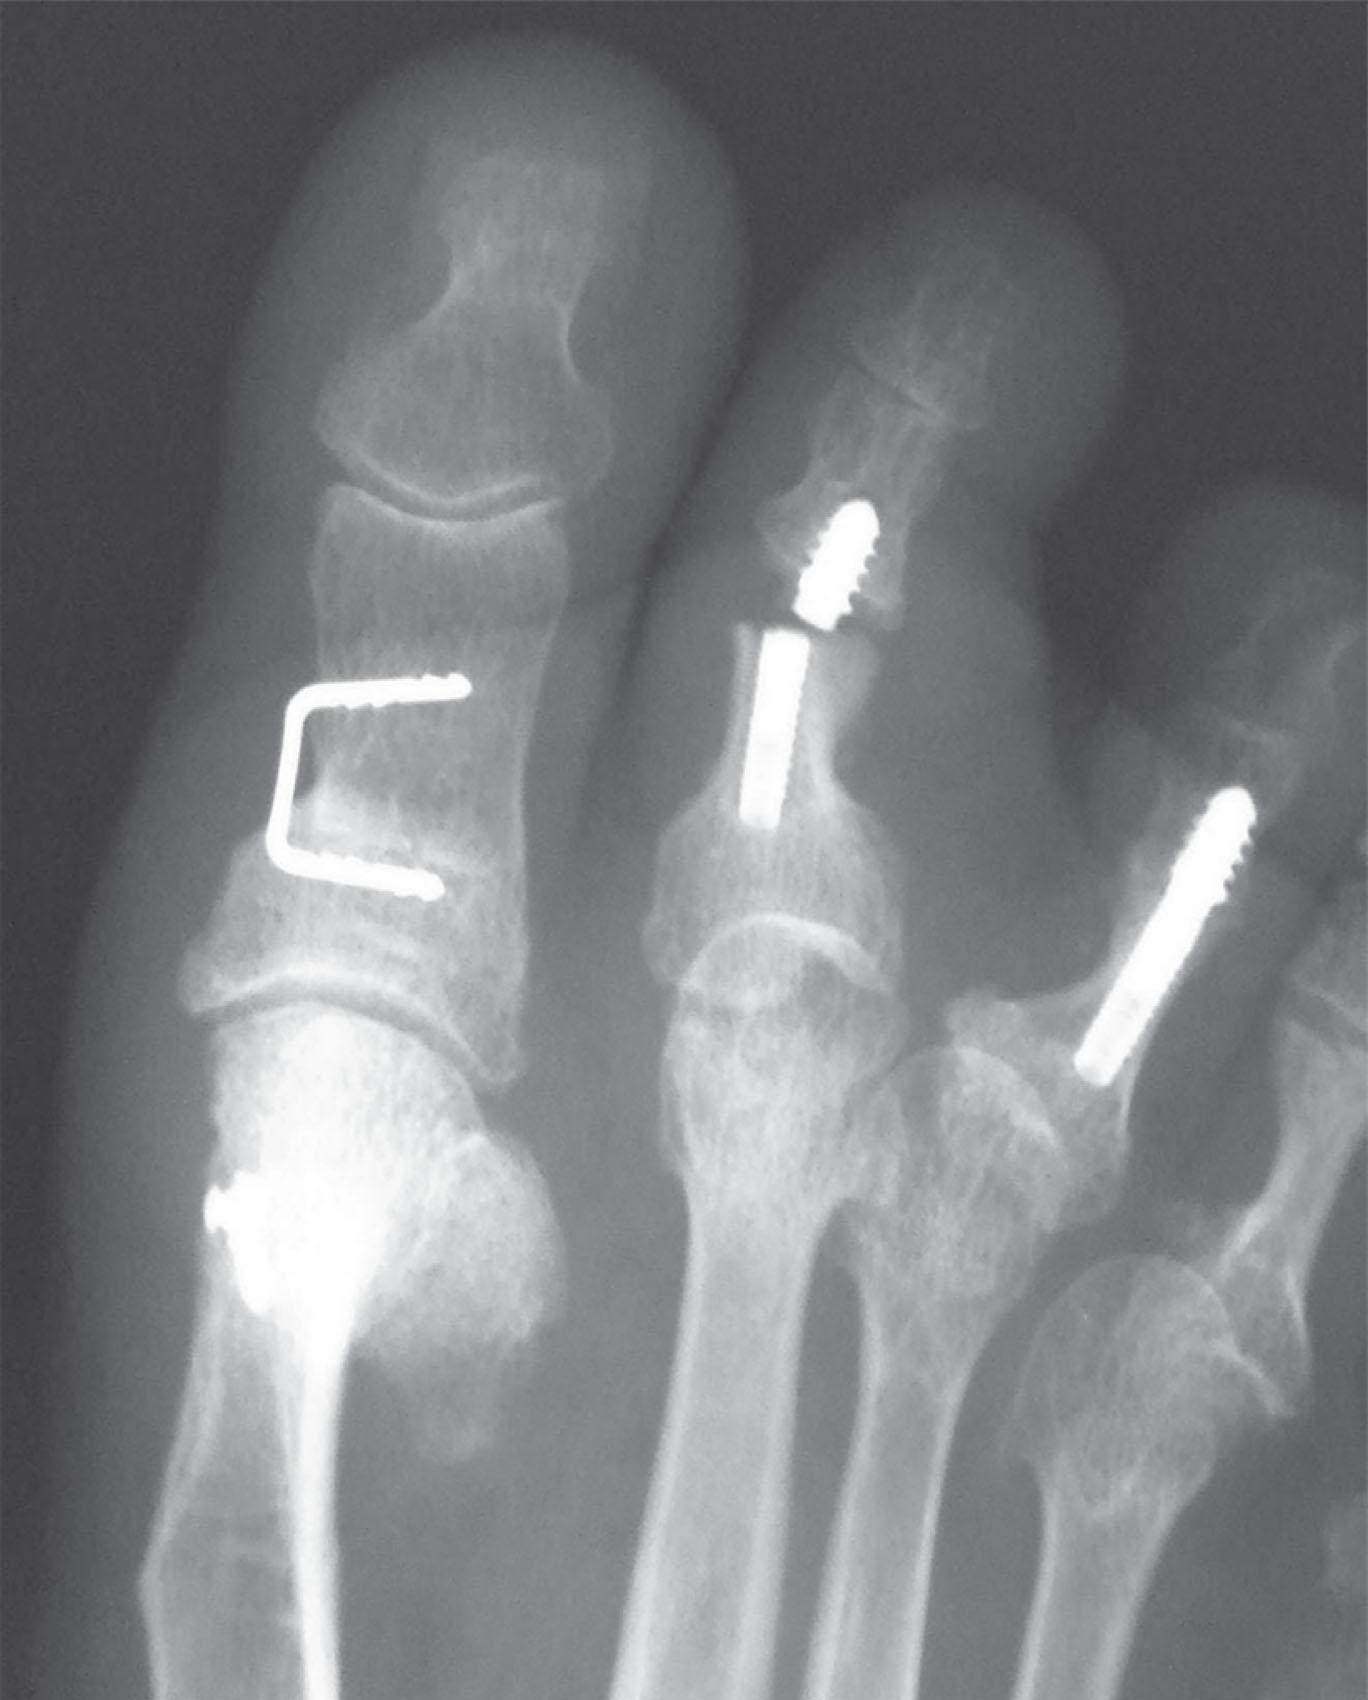

Intramedullary fixation for hammer toe correction has been advocated in an effort to secure permanent fixation without the use of Kirschner wires. Absorbable implants, screw fixation ( Figs. 9-41 and 9-42 ), wire loops, and other permanent intramedullary devices ( Fig. 9-43 ) have all been reported.

Fig. 9-41, Examples on intramedullary screws for hammer toe fixation. A , Placement of intramedullary Kirschner wire and cannulated screw from the tip of the toe. B , Cannulated screw fixation. C , Preoperative radiograph demonstrating subluxation of second and third metatarsophalangeal (MTP) joints and hammer toes of second and third toes. D , After intramedullary hammer toe fixation and distal osteotomies of second and third metatarsals. E , Intramedullary Herbert-type screws placed from the tips of the toes for treatment of hammer toe deformities. Note marked lesser MTP joint subluxation.